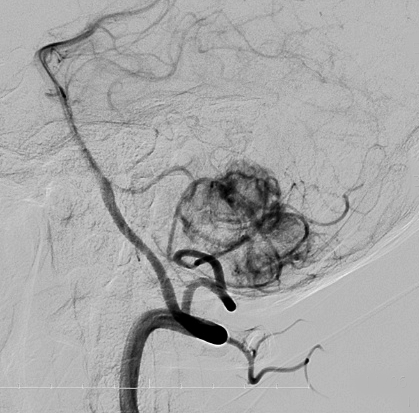

- 椎骨動脈撮影では,著明な腫瘍濃染像(血管がいっぱい)がみられて確定診断が可能です

ものすごく難しい血管芽腫

これも血管芽腫です。おそらく小脳発生なのでしょうが,延髄の両側に強く癒着していて延髄の血管も腫瘍の中に入っていて,腫瘍血管には動脈瘤も合併していて破裂しました。この腫瘍を摘出するのは不可能にも思えましたが,無事にできました(下の写真)。患者さんも私もへとへとになりました。 でも,このような血管芽腫の手術はうまく行くとは限りません,手術不可能と考えた方がいいかもしれないと今でも思っています。手術すると決めればものすごく高いリスクを患者さんも外科医も背負うことになります。放射線治療をして治るサイズではないので他に治療法はありませんが (>_<) 大きな血管芽腫を手術する提案をされたら,少なくとも執刀医の経験数は尋ねましょう。

フォンヒッペルリンドウ病に合併した大きな右小脳半球血管芽腫です。大きなものでは静脈環流障害(鬱滞)のために脳浮腫を来すことが多いし,その分,手術時の静脈圧が高くて止血が難しいと考えなければなりません。水頭症を呈して症状は重篤でしたが,右後頭窩開頭で比較的簡単に全摘出できて回復しました。小脳半球に生じるものは手術で大きな障害を残すことはほとんどなく術後の症状症状の回復も順調なことが多いです。

同じ患者さんです。上記の手術の5年後に新たな血管芽腫が激しく増大しました。これは小脳虫部なので両側の上小脳動脈がfeeding arteryとなります。bilateral occipital transtentorial approachという特殊な手術方法でしか摘出できません。幸いこの腫瘍も無事に全摘出できました。

真偽のほどは解りませんが頭の中で血液が流れる音がするというのが主訴です。その後に軽度の歩行失調と構語障害が出て発見されました。この程度のものでもAVMと同じように血管雑音を自覚することがあるのかもしれません。画像をよく見ると右の小脳扁桃のもので,延髄はただ圧迫されているだけです。血管芽腫はエリスロポエチンを産生して多血症になることがあるのですが,この患者さんは16.6 MIU/mlで正常値でした。

右のPICAが主たるfeeding arteryです。でもPICAのretromedullary segmentからshort feedersが流入していますから,油断をすると延髄背側障害という厳しい手術合併症を生じる可能性は十分あります。この腫瘍は正中後頭下開頭で全摘出できましたし,神経脱落症状を残していません。難易度は中等度のものです。